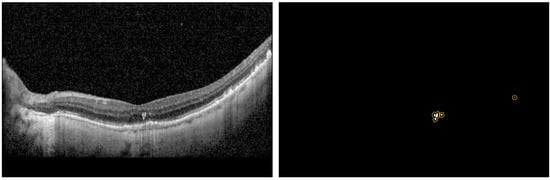

The dataset consists of 3557 B-Scans and their corresponding ground truth (GT) masks collected from 600 DR and 2957 AMD subjects at a tertiary center at the University Eye Hospital Bonn, University of Bonn, Germany. Spectral-domain OCT imaging was performed using a Spectralis HRA+OCT (digital image resolution, 496 × 768 pixels; Heidelberg Engineering, Heidelberg, Germany) device, through the fovea. A minimum signal strength of 7 out of 10 was considered for the inclusion of data. Data was de-identified and exported in an anonymized manner. This study adhered to the tenets of the Declaration of Helsinki and was approved by the local institutional review boards at the University of Bonn (Bonn) and the University of Illinois at Chicago (UIC). The GT was generated by one grader at Bonn (MP) and two graders at UIC (MM and AS—supervised by MM). ImageJ was used to manually annotate the boundaries of HRFs found in the outer nuclear and/or outer plexiform layers for each OCT image. We measured the variability of the manual segmentation of HRFs between two sets of graders and evaluated the accuracy of the DL model compared to manual segmentation by both teams. Each of the B-Scans contained at least one HRF. The size of the B-Scans and masks are 496 × 768 pixels. The original dataset was sorted and shuffled with a random state and split 80/20 into a train and test dataset. Furthermore, the train dataset was split 80/20 to create a validation dataset. The final train, validation, and test datasets consisted of 2276, 569, and 217 B-Scans and their corresponding GT masks, respectively. We trained and evaluated the segmentation model using three schemes: with full B-Scan images, cropped B-Scan images, and patches of B-Scan images, as shown in Figure 1.

The purpose of the segmentation model was to segment the location of the HRF in the B-Scan. The B-Scan patches from the train and validation dataset that were labeled as HRF were used to train and validate our model. Our segmentation model was trained using a batch size of 10 (small due to memory limitations) and a learning rate of 10−4 (small as it allows the model to learn more optimally) and was trained for 1500 epochs. The segmentation model used the U-Net architecture and was tested on multiple image types as shown in Figure 1. Additionally, we conducted rigorous hypertuning, including testing different loss functions and backbones in order to achieve the highest performance. The multiple loss functions we evaluated included dice loss, Jaccard loss, and Binary Cross Entropy. Additionally, the multiple backbones we evaluated included ResNet34, InceptionV3, DenseNet169, and EfficientNetB4 with augmentations such as dilation, rotation, brightness, and horizontal flip.

Table 3 shows the segmentation results for the three image types and loss functions we tested using the U-Net model with the backbone of ResNet34. The best performance for IOU and Precision were obtained with Patches image type and Binary Cross Entropy loss function. Some examples of the segmentation prediction are shown in Figure 5.

Figure 1. Three training image types—(a) Full image; (b) Cropped image; (c) Patches.

Figure 5. Example HRF segmentation results. Yellow is the prediction over white ground truth annotations.